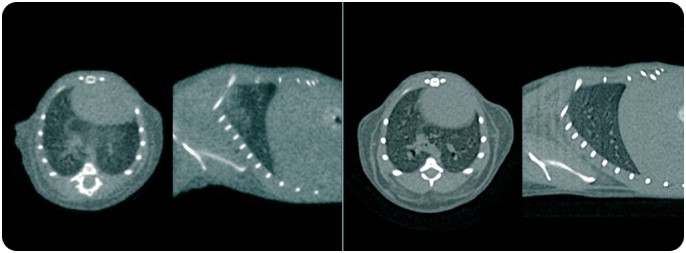

Mice Pulmonary

Cardiovascular Imaging

PET/CT Si78 in Rat

Abdomen & Thorax